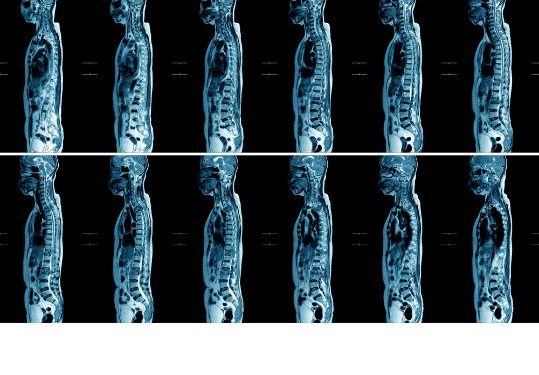

Bone metastases are most commonly found in the ribs, pelvis, and femur. X-rays and CT scans can also be used to diagnose these metastases. MRIs are also sometimes used, especially if the CT scan results are unclear.